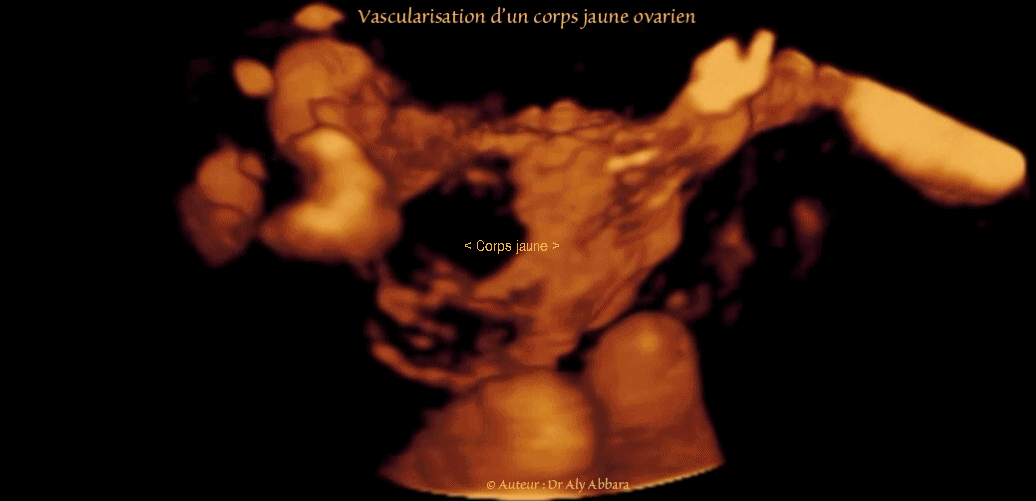

Vidéo et image échographiques en 3D montrant les caractéristiques de la vascularisation (analysée en mode Doppler-Energie) d'un corps jaune dans l'ovaire droit :

• Le corps jaune est de 30 mm de grand axe, à centre enkysté.

• En périphérique (au niveau des thèque interne et externe) on identifie, grâce au Doppler-Energie, un important réseau de néovascularisation provenant des deux réseaux vasculaires vascularisant l'ovaire :

• le réseau vasculaire lombo-ovarien

• le réseau vasculaire utéro-ovarien .

• Cette importante néovascularisation autour du corps jaune, se situe histologiquement dans les deux thèques (interne et externe) qui enveloppent la granulosa du corps jaune.

• L'ovaire juxtapose latéralement les vaisseaux iliaques internes (la veine iliaque interne "VII" et l’artère iliaque interne "AII ").